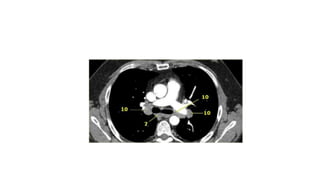

CT chest

Homogenous , high

Attenuation

Meniscoid

0-20 HU

CT chest Homogenous ,high Attenuation Meniscoid 0-20 HU